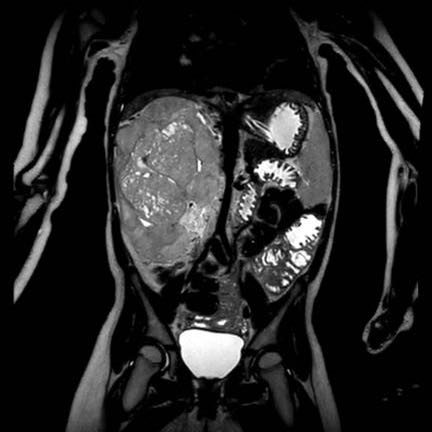

Ca lâm sàng 1

Hình ảnh chuỗi xung T2W mặt phẳng coronal cho thấy một khối u không đồng nhất ở thận trái với các thành phần nang nhỏ.

Khối u ngấm thuốc kém hơn so với phần nhu mô thận bình thường còn lại ở ngoại vi.

Các thành phần đặc của khối u cho thấy hạn chế khuếch tán rõ rệt (mũi tên).

Đây là u Wilms ở bé trai năm tuổi. Hóa trị tiền phẫu được thực hiện theo phác đồ Umbrella của SIOP-RTSG, sau đó tiến hành cắt thận.